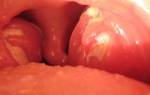

Изображение тонзиллита показывает воспаление миндалин с неровной поверхностью, покрытой гнойными отложениями

Инфекционная патология, вызванная активностью бактерий, относится к бактериальному типу заболевания. Обычно для лечения используют антибиотики. При таком поражении может развиться гнойный тонзиллит, при котором гноем покрываются воспаленные миндалины, как показано на изображении.